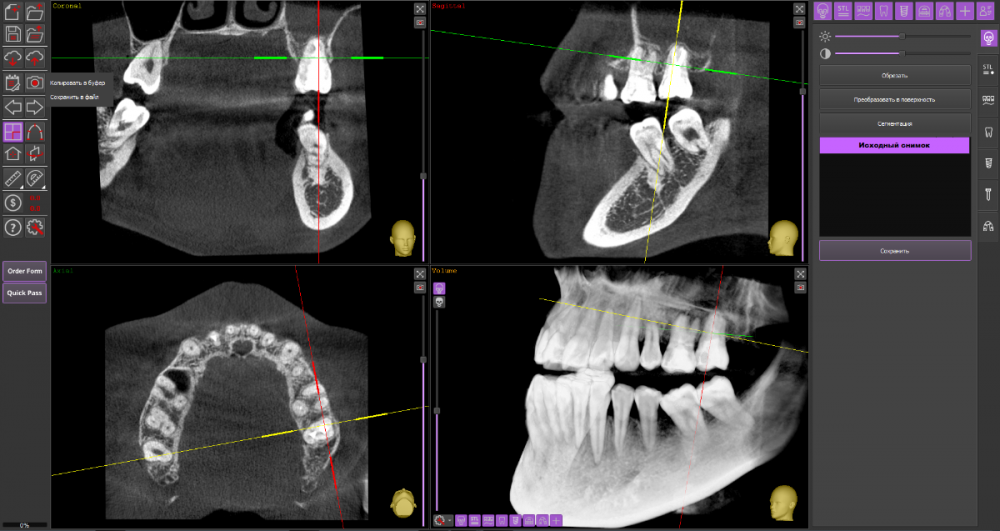

Киста 6,7 слева и гайморит

Зубы: лечение начала в конце декабря. на кт обнаружили кисту над 6,7 зубами слева. 7 зуб заходит в пазуху. Начали лечить 6, сказали что попробуют спасти, заложили лекарство на 2 недели. Также стоял ортодонтический имплантат рядом с 7 зубом, сказали что находится очень близко к корню зуба и пазухе. Имплант удалили.

3. третьи сказали что надо вырывать 6,7 зубы. Так как воспалена нижняя стенка пазухи и истончается кость. Оставить открытым после удавления и дать вытечь гною из пазухи а затем ставить имплантаты

КТ

Думаю, стоит пока попробовать консервативное лечение у стоматолога-терапевта.

27_1.thumb.png.f14a8928c9d8a1eb86e7447fa41147e0.png